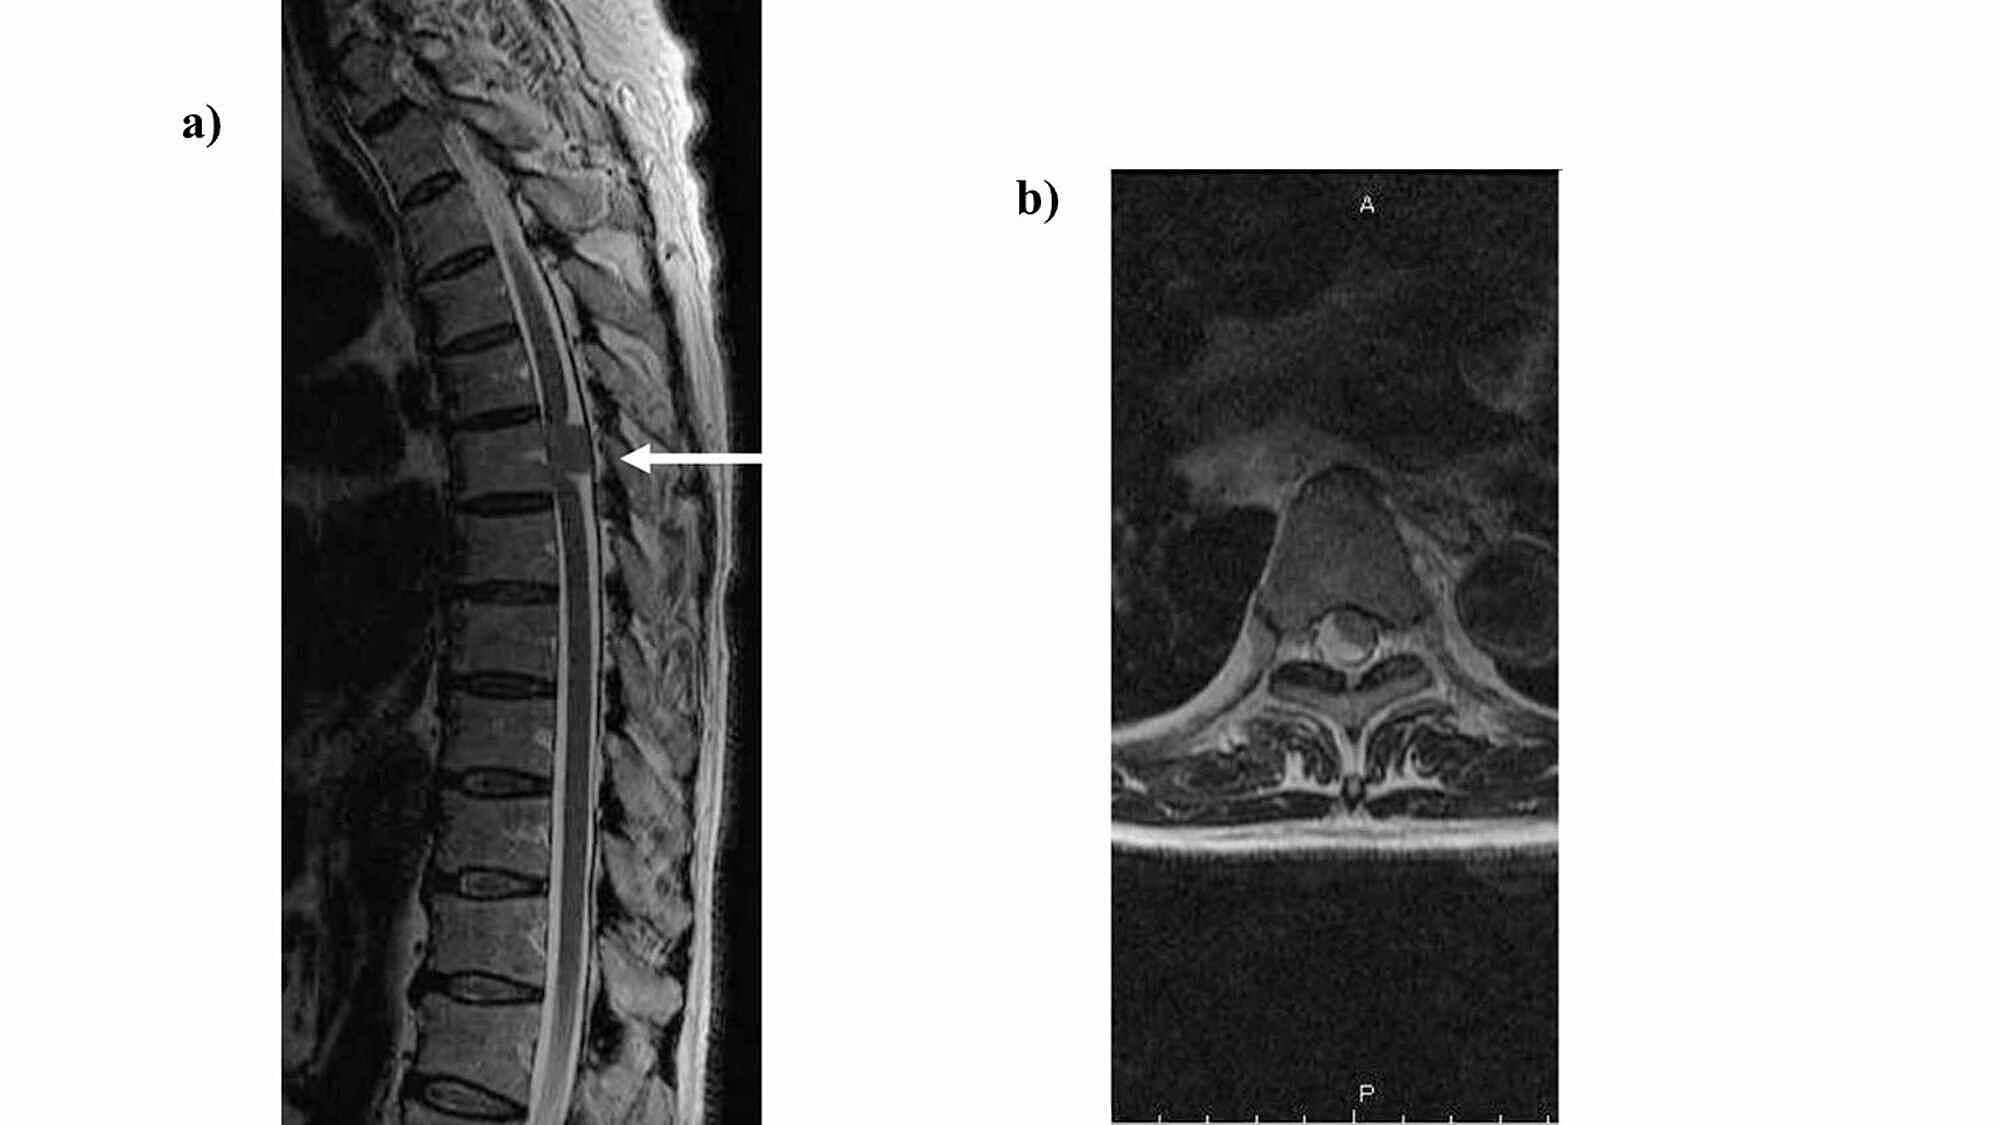

Manual muscle testing showed a decrease in muscle strength in both lower limbs as well as a decrease in deep and superficial sensations in the foot soles to the lower legs. An intradural extramedullary tumor in the Th6 region of the thoracic spine was identified via thoracic spine magnetic resonance imaging; the patient underwent orthopedic surgery, and tumor resection was performed on May 21. Pathological results led to the diagnosis of meningioma, and the patient was transferred to the convalescent rehabilitation ward of our institution on June 8, 18 days after surgery.

Thoracic spinal cord magnetic resonance imaging was performed (Figure 1-2). Based on the aforementioned findings, the following four points were identified as issues: (ⅰ) ataxic gait derived from position sense disturbance due to posterior compression from the tumor, (ⅱ) requirement of a walker due to muscle weakness in both lower limbs, (ⅲ) minimal assistance needed for activities of daily living, and (ⅳ) difficulty returning to work. The following were proposed rehabilitation treatment plans: range of motion training, muscle strength enhancement training, outdoor walking, stair climbing, applied movement training, balance motion acquisition training, activities of daily living, housework, and standing walking under a weight load used to enable a return to work.